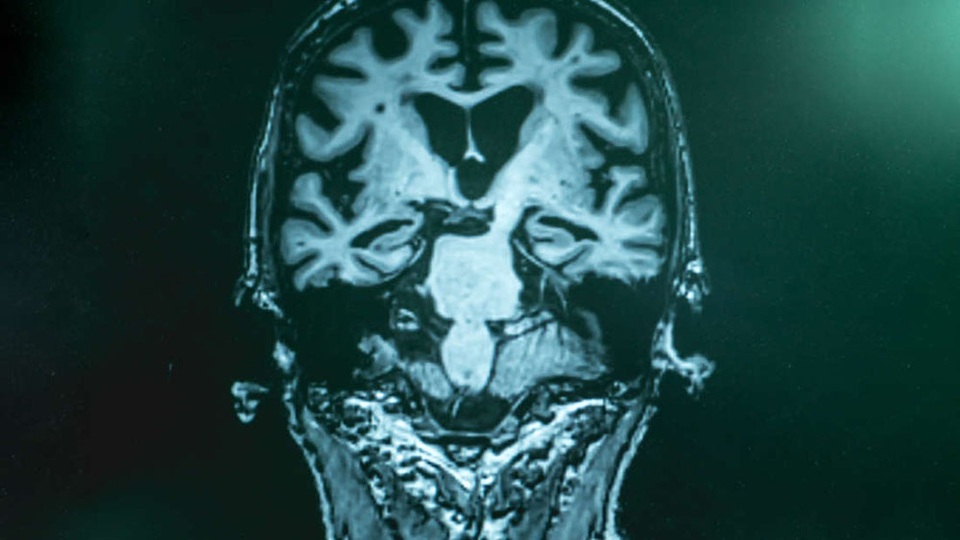

Một vấn đề lớn ảnh hưởng đến nghiên cứu của Alzheimer là gần như không thể xác định được căn bệnh này ở giai đoạn sớm nhất. Vì vậy, thông thường, tại thời điểm được phát hiện, các triệu chứng suy nhược đã xuất hiện và tại thời điểm đó, nó có thể đã quá muộn.

Điều thú vị là, kết quả xét nghiệm máu của một số bệnh nhân ban đầu được cho là dương tính giả, trên thực tế, là dương tính thật. Các nhà nghiên cứu đã bác bỏ những kết quả này vì chúng không phù hợp với chụp PET (âm tính) của bệnh nhân. Tuy nhiên, các lần quét não sau đó đã xác nhận rằng họ đã hoàn toàn đúng. Điều này cho thấy xét nghiệm máu đã phát hiện căn bệnh ở giai đoạn sớm hơn và đáng tin cậy hơn so với chụp PET tiêu chuẩn vàng hiện tại.

Các chuyên gia rằng để quản lý hoặc điều trị bệnh Alzheimer, thực tế cần phải được phát hiện càng sớm càng tốt trước khi các triệu chứng bắt đầu xuất hiện. Vào thời điểm các triệu chứng xuất hiện, não có thể bị tổn thương quá mức để khắc phục.